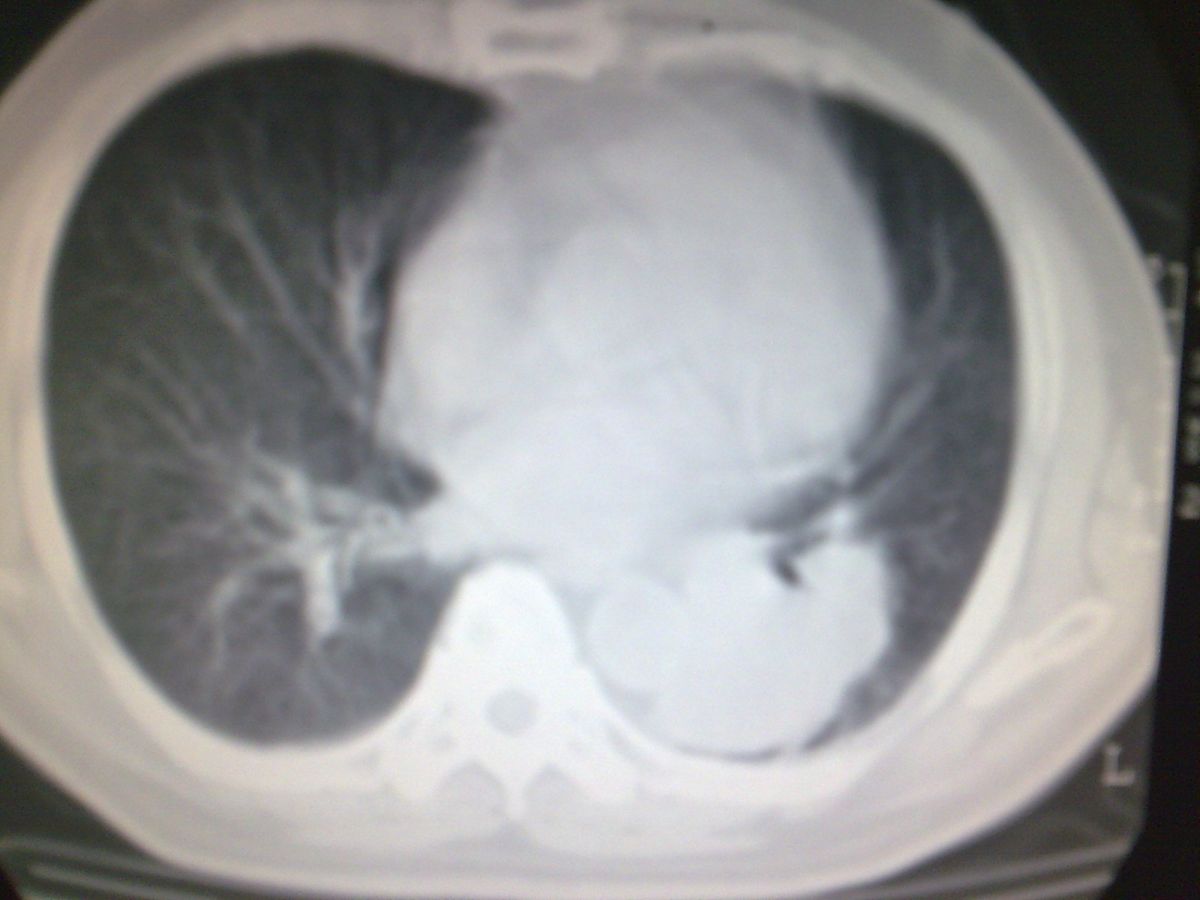

标题: CT19282:男性,70岁,咳血, [打印本页]

标题: CT19282:男性,70岁,咳血,

图片少了些,考虑周围性肺癌

考虑周围性肺癌

周围型肺癌。

考虑左下肺周围性肺癌。

考虑左下周围型肺癌可能性大。

考虑左肺下叶周围型肺癌可能。